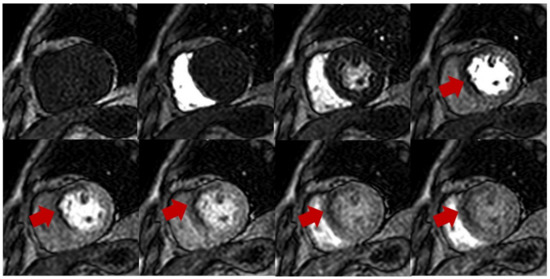

Dynamic contrast-enhanced perfusion imaging is the basic technique of this exam, which captures the signal changes of contrast passing through the chambers of the heart and myocardium. This method uses electrocardiogram-gated fast T1-sensitive imaging and can be performed both during stress and rest [12]. Typical perfusion sequences used are saturation-recovery with balanced steady-state free precession (SSFP), gradient echo (GRE), or GRE-echo planar hybrid readout. Slice thickness is typically 8–10 mm with temporal resolution around 100–125 ms, usually acquiring every heartbeat, but acquired across two heartbeats in higher heart rates. Myocardial ischemia is assessed during vasodilation, which is commonly induced by injecting adenosine, dipyridamole, regadenoson, or adenosine triphosphate (ATP) [13]. Gadolinium-based contrast is then injected (0.05–0.1 mmol/kg, 3–7 mL/s), followed by a saline flush (≥30 mL) into a peripheral vein after achieving hyperemia to visualise the trajectory of blood flow and myocardial perfusion supplied by normal coronary arteries versus diseased vessels. Ischemic myocardium therefore shows slower perfusion and a decreased T1 signal when compared to normal segments (Figure 1).

Stress perfusion showing myocardial ischemia using adenosine. Upper and lower panel shows a single basal ventricular short axis slice acquired during stress perfusion imaging. The gadolinium contrast first enters the right ventricle, then the left ventricle, and finally perfuses the myocardium. Red arrow shows myocardial ischemia in the basal anteroseptal wall with decreased T1 signal compared with normal segments.